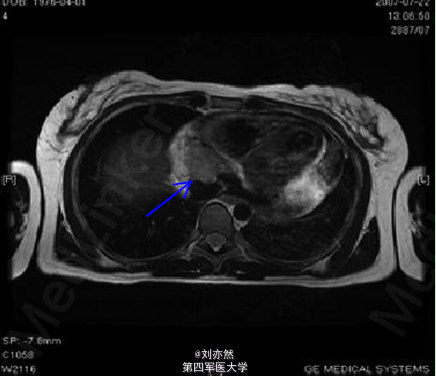

心脏血管肉瘤两例

一例经食管心动超声示:血管肉瘤位于心包内,并浸润心房壁(图1)。一例MRI示肿块位于心包内,邻近下腔静脉及右心房,并造成心包积液(图2)。 讨论:心脏原发性肿瘤极少见,其中肉瘤为最常见的类型。影像学检查结合病理学检查确诊病例。 引自:Beraldo DO, Melo JF et al. World J Gastroenterol. 2013 Dec 14;19(46):8789-92.